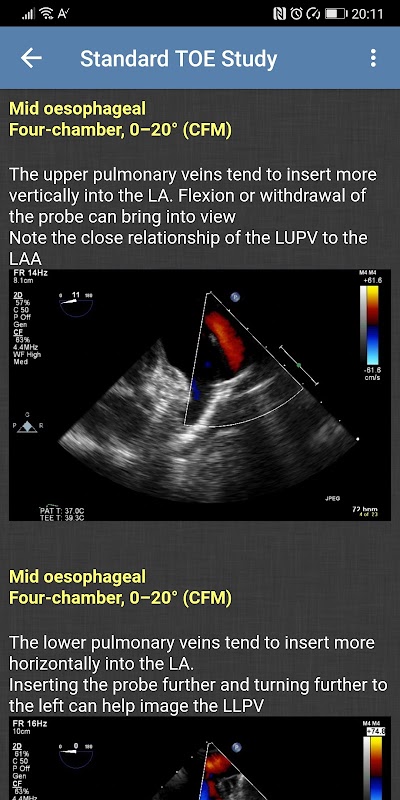

- การศึกษา TOE มาตรฐาน